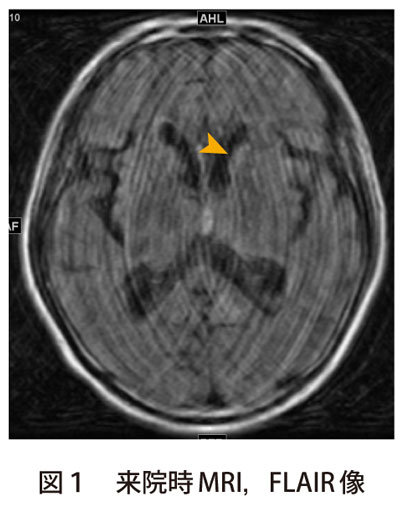

症例4 診断と解説